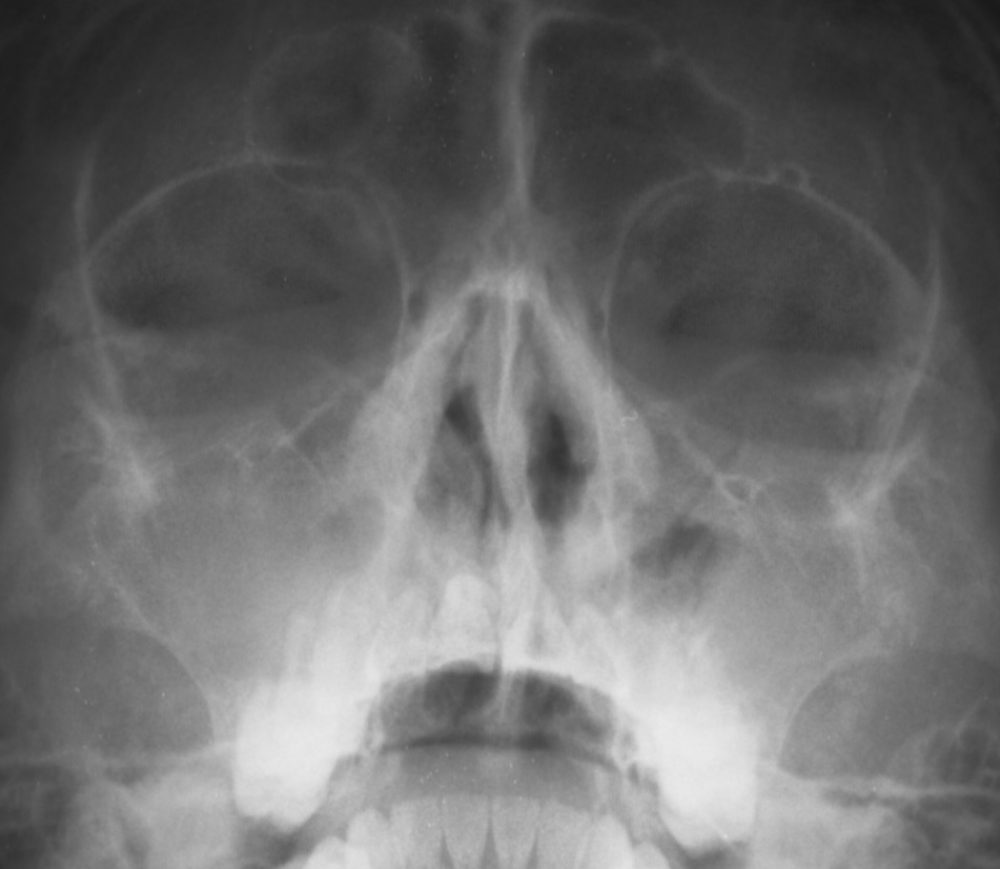

(レントゲン検査)←CTに比べて情報は限定的、検査料は安価。

超音波検査は、小さいお子さんにも繰り返し行うことができ、妊娠中の方でも行える安全な検査です。しかし、上顎洞以外の副鼻腔については診断できません。レントゲンは、篩骨洞や前頭洞についてもある程度分かりますが、CTほど詳しい正確なところまでは分かりません。また、蝶形骨洞については、レントゲンでは全く分からず、CTが必要です。

CTによって、一般のレントゲンでは分からない、いろいろな詳しいことを知ることができます。情報の量と正確さについては、CTと一般のレントゲンとでは圧倒的な差があります。さらにコーンビームCTなら、放射線被曝も一般のレントゲン同様わずかです。

幼小児の副鼻腔炎と大人の急性副鼻腔炎は、主として上顎洞に起きますので、超音波検査で十分診断できます。年長児や大人の慢性副鼻腔炎では、レントゲンが必要な場合もありますが、それも正確な診断には不十分です。正確で詳細な診断には、CTが必要です。

CTでは、一般のレントゲンより格段に詳細な画像が得られ、レントゲンでは分からない蝶形骨洞の炎症や、歯性上顎道炎の診断も可能です。当院では従来のCTより放射線被曝量が格段に少なく、検査料も安い、コーンビームCTを、2021年10月から導入しました。